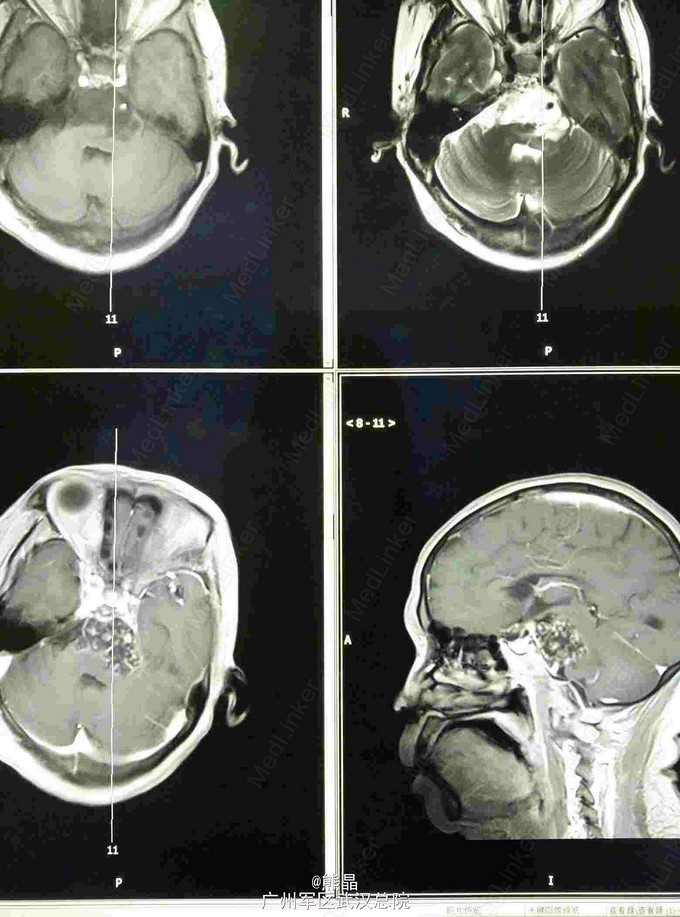

查体:左上肢屈曲状态,不能伸直 CT:碟鞍区及脑干区可见大片状密度减低影,右侧碟鞍骨质有破坏征象 MRI:肿块呈长T1长T2信号,增强呈蜂窝状强化

脊索瘤 行手术切除